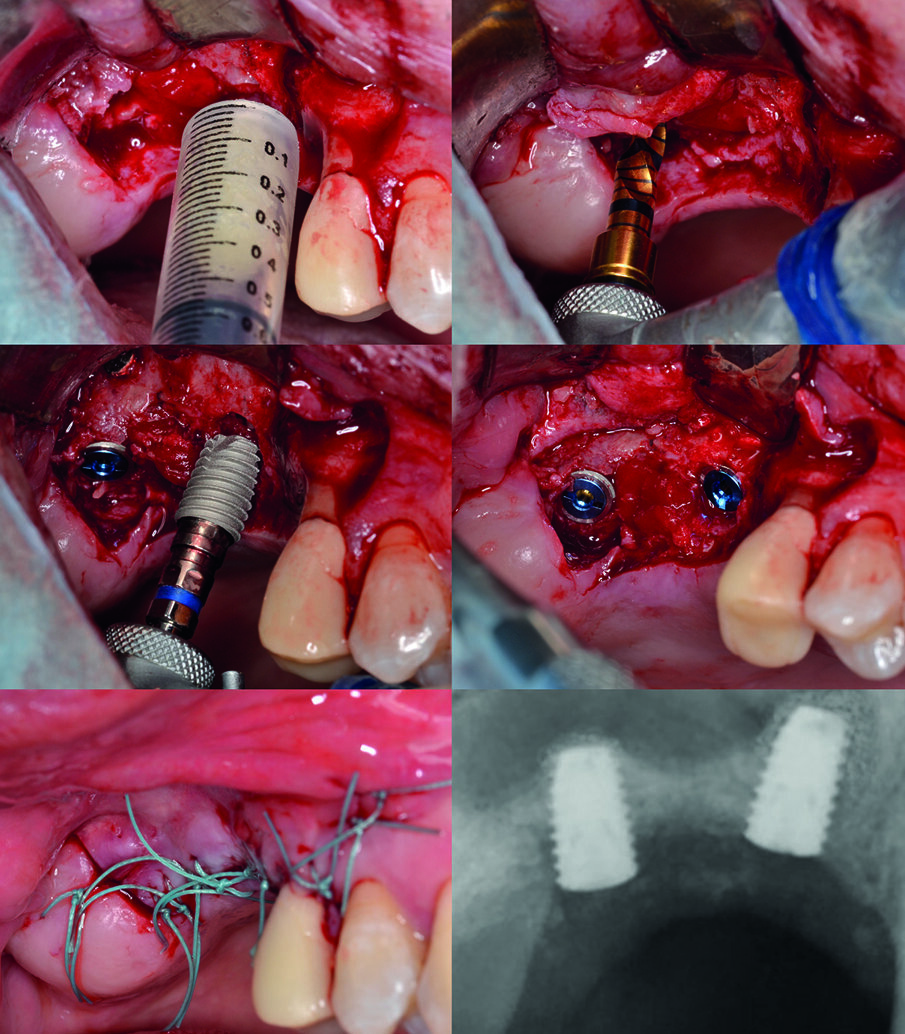

L’area di intervento è stata anestetizzata utilizzando articaina cloridrato 40 mg con adrenalina 1:100000. Si è proceduto quindi a sollevare un lembo trapezoidale a tutto spessore mediante un’incisione crestale anticipata palatalmente. Dopo avere posizionato una dima radiologica, appositamente fabbricata, si è proceduto a marcare i siti implantari sulla corticale ossea in corrispondenza dei reperi metallici, e a preparare i tunnel implantari per mezzo del sistema “Crestal Approach Sinus Kit” (BetaPharm, Via Brigata Berto 10 - 16030 Cogorno - Italia). Da notare che l’altezza ossea residua (Residual Bone Height o RBH) inferiormente al seno mascellare variava tra i 3,66 mm e i 2,84 mm.

Il clivaggio e sollevamento della membrana sinusale sono stati eseguiti utilizzando l’inserto atraumatico dedicato “Hydro Membrane Lift” (Fig. 2). L’innesto della pasta ossea (ACT-MLD010, Activabone Mouldable Paste, Bioteck S.p.A., Vicenza, Italia) è stato eseguito estrudendola dalla siringa direttamente nei tunnel implantari, mediante apporti consecutivi di piccola entità; l’espansione e la compattazione del biomateriale all’interno del sito di innesto sono state ottenute utilizzando un inserto denominato Rotary Plugger, sempre incluso nel “Crestal Approach Sinus Kit” (BetaPharm, Via Brigata Berto 10 - 16030 Cogorno - Italia). Sono stati quindi posizionati due impianti di dimensione 4,5 x 7 mm (Shinhung Luna, BetaPharm, Via Brigata Berto 10 - 16030 Cogorno - Italia), e i lembi sono stati suturati utilizzando una sutura non riassorbibile in poliestere 4-0 (Ethibond Excel, Ethicon Italia, Via del Mare, 46, 00040 Pomezia, Italia) (Fig. 3). Pur senza sottopreparazione e nonostante il ridotto spessore della cresta residua, è stato registrato un torque di inserimento soddisfacente per entrambi gli impianti (45 e 55 Ncm rispettivamente per l’impianto mesiale e distale). La radiografia endorale di controllo acquisita al termine della chirurgia mostrava entrambi gli impianti circondati dal materiale di innesto anche in posizione apicale.

Fig. 2 - Creazione dei tunnel implantari e sollevamento della membrana sinusale. La posizione dei tunnel implantari è marcata sulla cresta vestibolare con l’aiuto di una dima radiografica; successivamente alla preparazione dei tunnel, si procede al sollevamento della membrana sinusale attraverso il sistema idropneumatico.

Fig. 3 - Innesto osseo e posizionamento degli impianti. La pasta ossea viene estrusa dalla siringa direttamente nei tunnel implantari; per favorire il riempimento dello spazio al di sotto della membrana, l’innesto è eseguito mediante apporti consecutivi di ridotta entità e, al termine, con l’ausilio di inserti tipo Rotary Plugger. Segue il posizionamento degli impianti e la sutura.